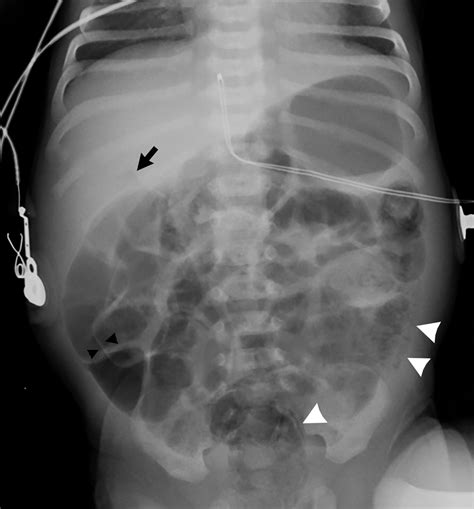

The human gastrointestinal tract naturally contains a certain amount of gas. This gas is a byproduct of digestion, the breakdown of food by bacteria in the colon, and the air we swallow while eating or drinking. A nonobstructive bowel gas pattern refers to the typical, expected distribution of gas throughout the intestines as seen on imaging, which does not indicate a clinical obstruction.

In a healthy individual, gas moves through the bowels alongside digested food and stool, eventually being passed as flatus or absorbed. When a radiologist describes the pattern as "nonobstructive," they are confirming that the gas is scattered in a way that is consistent with normal physiological function, rather than being trapped in a dilated loop that indicates a mechanical blockage.

The primary concern when a patient presents with significant abdominal pain is a bowel obstruction. A bowel obstruction is a serious condition where part of the small or large intestine is blocked, preventing the passage of food, gas, and stool. Left untreated, it can lead to bowel perforation or tissue necrosis.